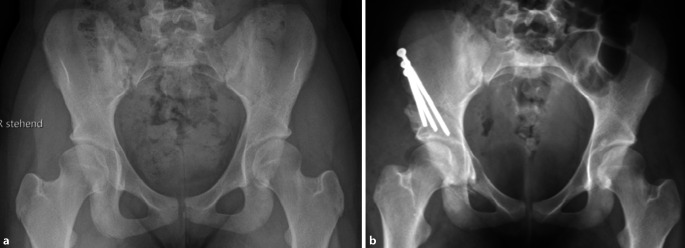

Um die Stabilität der postoperativen Fixation und die Knochenheilung zu überprüfen, sollte vor der Vollbelastung nach der 4. respektive nach der 6. postoperativen Woche eine a.-p.-Beckenübersichtsröntgenaufnahme angefertigt werden (Abb. 18a). Eine weitere a.-p.-Beckenübersichtsröntgenaufnahme kann bei Bedarf nach dem 3. bis 6. postoperativen Monat durchgeführt werden (Abb. 18b).

In der vorliegenden Arbeit präsentieren wir die Ergebnisse der ersten 39 Patienten (36 Frauen und 3 Männer), die zwischen Januar 2016 und August 2017 vom Seniorautor operativ mittels oben genannter Technik versorgt wurden, zu einem mittleren Follow-up von 3,5 (3 bis 4,5) Jahren. Das durchschnittliche Alter zum Operationszeitpunkt betrug 23 (16 bis 42) Jahre, und der durchschnittliche Body Mass Index (BMI) lag bei 27 (18–36) kg/m2. Die durchschnittliche Operationsdauer betrug 88 (57 bis 142) Minuten. Bezüglich der radiologischen Parameter konnten der LCE-Winkel signifikant von präoperativ 16,1° (7–24°) auf postoperativ 30,5° (25–37°) (p < 0,0001) und der AC-Winkel signifikant von präoperativ 13,2° (2–25,3°) auf postoperativ 2,8° (−3–13°) (p < 0,0001) korrigiert werden.